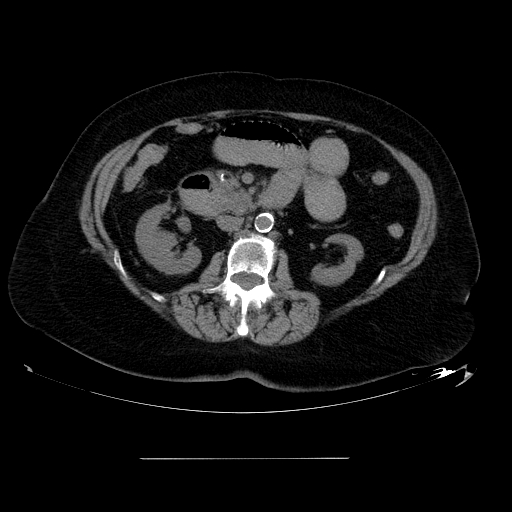

Gallstones are typically radiolucent (10 percent of gallstones are radiopaque because of associated calcium).

Bilirubin stones are normally radiopaque.